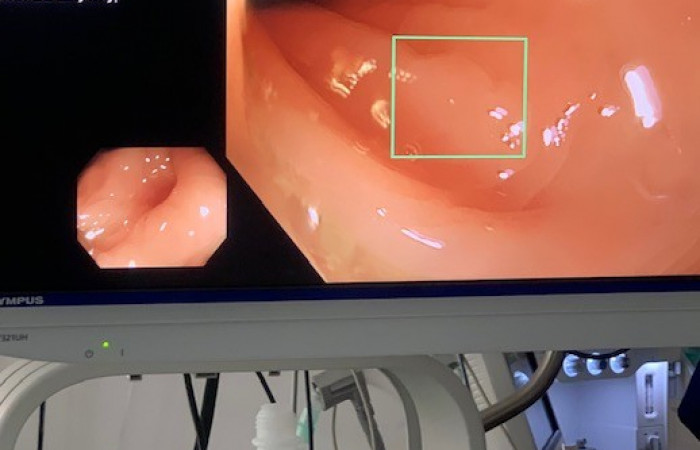

Dzięki specjalnej aplikacji system EVIS X1 w czasie rzeczywistym wspomaga wykrywanie zmian chorobowych podczas kolonoskopii. Dla ludzkiego oka niektóre zmiany nie zawsze są widoczne. I właśnie tutaj wkracza sztuczna inteligencja. Przy użyciu tej technologii kolosalnie zmienia się dokładność diagnostyczna w rozpoznawaniu wczesnych zmian nowotworowych przewodu pokarmowego.

- To taki drugi „operator”, który cały czas ma wzrok skupiony na badanym polu i nawet na ułamek sekundy nie spuszcza go z oka – wyjaśnia prof. Kukla. - W momencie, gdy system zauważy coś podejrzanego, co jego zdaniem może być patologią, zaznacza ten fragment obrazu prostokątem. To sygnał dla operatora, by dokładniej ocenić wskazany fragment śluzówki jelita. Operator może uznać obraz za normę lub patologię i podjąć adekwatne działania.